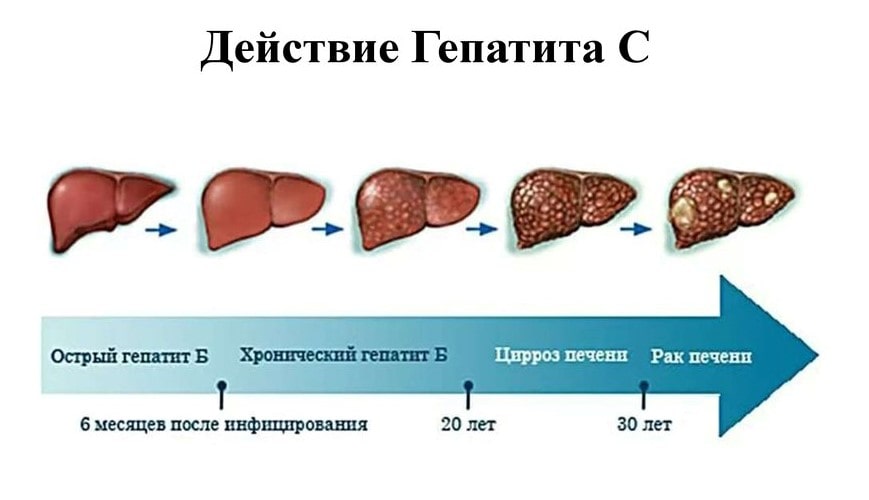

Признаки заболеваний печени: Важные симптомы и рекомендации